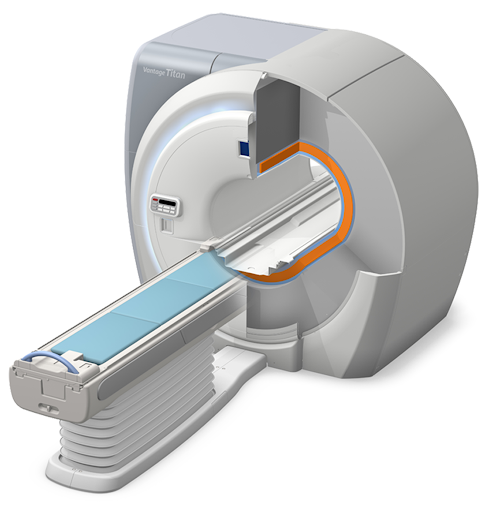

Vantage Titan 3Т – современный томограф, который позволяет проводить качественные диагностические исследования.

Технология снижения шумов Pianissimo. Специальная вакуумная камера вокруг градиентной катушки подавляет акустические шумы, делая исследование более тихим и приятным.

Диаметр апертуры в 71 см, ультракороткий канал магнита, и технология Pianissimo создают максимальное удобство для пациентов во время МР-исследования.

Технология Speeder, позволяет параллельно обрабатывать и собирать данные, что в 16 раз сокращает время исследования

Технология EasyTech позволяет настроить сканирование на определенные анатомические ориентиры, тем самым улучшить воспроизводимость сканирующих плоскостей независимо от положения пациента

Матричная технология катушек Atlas сканирует пациента без переукладок и смены катушек

Технология Multi-phase Transmittion, оптимизирующая изображение в брюшной полости

Усовершенствованные методы неконтрастной МР томографии снижают риски для некоторых групп пациентов. С томографом Vantage Titan можно проводить такие исследования, как FBI, FBI Navi , CIA, SPEED, FSBB, Time-SLIP.

- Технология нулевого испарения гелия

- Матричная технология катушек Atlas